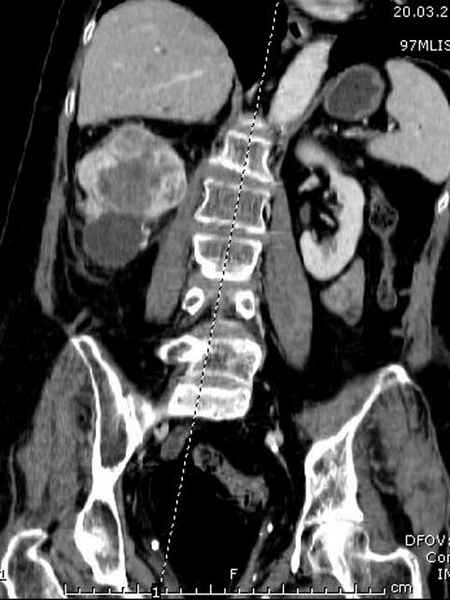

Со слов, больная ничем не болела, только последние 3 месяцев чувствовала боли в бедренной области. КТ брюшной полости подтвердил увеличенную правую почку. (5-6)